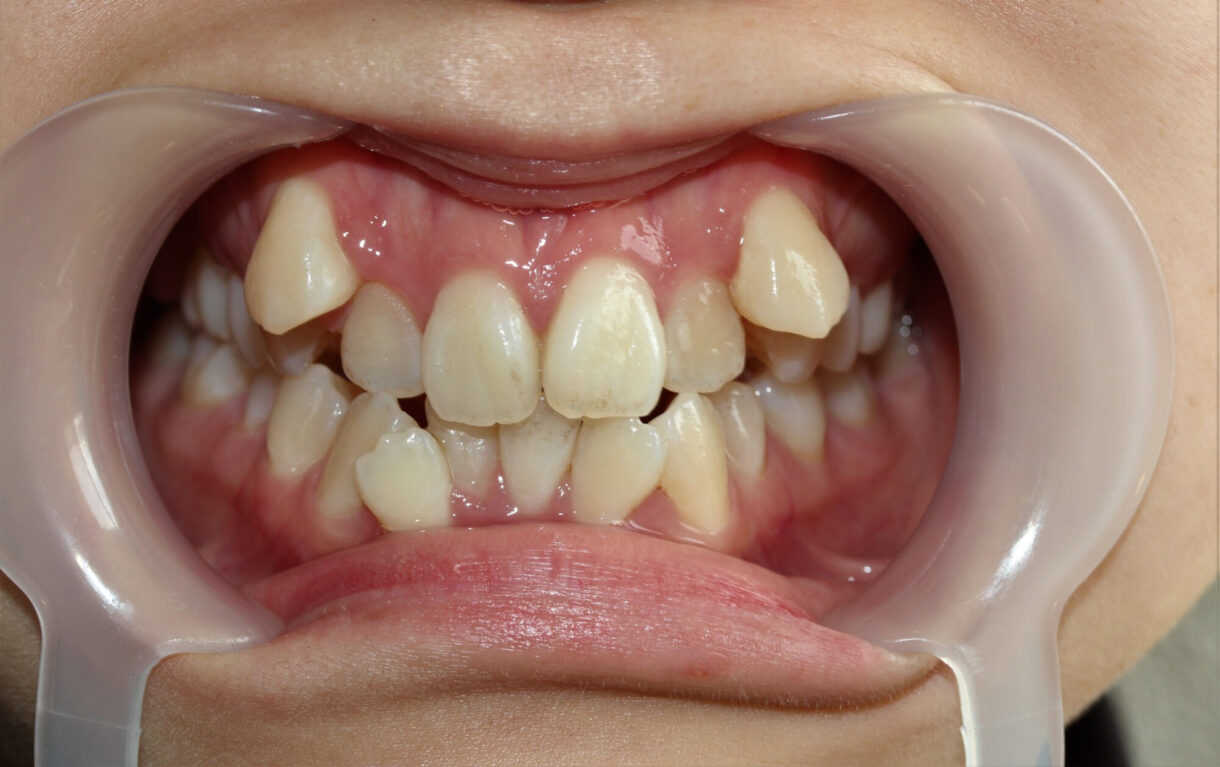

「犬歯」は前歯から数えて3番目の歯のことで、「八重歯」は本来の歯列から外側にはみ出した歯並びの状態を指します。なお、八重歯の正式名称は「低位唇側転移歯」です。

犬歯は八重歯になりやすいため、「犬歯=八重歯」と誤解されることがよくあります。しかし、本来の歯列から外側にはみ出していれば、犬歯でなくても八重歯とみなされます。

八重歯はチャームポイントとされることもあります。しかし、歯磨きがしにくくなるため、放置すると虫歯のリスクが高まるでしょう。噛み合わせにも悪影響をおよぼすため、矯正治療の対象となります。

4. 犬歯が八重歯になりやすい理由

犬歯が八重歯になりやすいことには、歯の生える順番が関係しています。犬歯は、すべての歯のなかで生えてくるのが最も遅い歯です。先に生えてくる歯がスペースを占領していた場合、犬歯は外側にはみ出すような状態、つまり八重歯にならざるを得ないのです。

同時に、顎の小ささも犬歯が八重歯になる要因の一つです。食生活などの影響で現代人は昔よりも顎が細くなっており、歯の生えるスペースがそもそも狭くなっています。そのため、犬歯が生える際に十分なスペースが残っていない場合が多いのです。